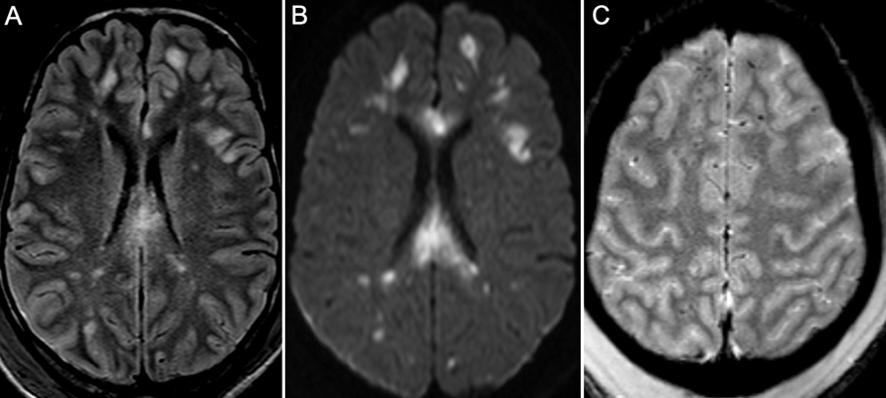

- Investigations:

- CT often normal initially

- MRI may reveal microhaemorrhages in deep brain structures